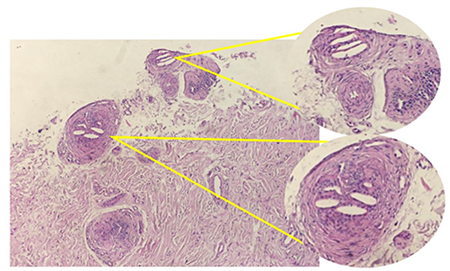

Para confirmar el diagnostico presuntivo se solicita una biopsia de piel, la cual informa un ateroembolismo de vasos arteriales de pequeño calibre en dermis profunda lo que corrobora el diagnostico (Figura 3).

La biopsia de piel confirma el diagnóstico de la enfermedad, con alto rendimiento de hasta un 92 %; en la histopatología es patognomónica la visualización dentro de los vasos de la unión dermohipodérmica de hendiduras alargadas biconvexas en forma de agujas9,13. Otras técnicas útiles son el examen del fondo de ojo encontrando cuerpos de Hollenhorst que son lesiones brillantes y refráctiles en bifurcaciones de arterias en retina, aunque sólo detecta la embolia por cristales de colesterol en un 6 % al 20 % de los casos. Hallazgo el cual estuvo presente en nuestro paciente. Se reportan casos en los cuales solo con el hallazgo en el examen de fondo de ojo fue suficiente para el diagnóstico y no llegaron a exámenes invasivos como biopsia14.